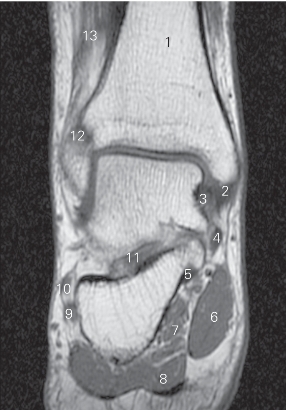

图5-56 经胫骨内髁的矢状断层MR T1加权图像

1 胫骨后肌 tibialis posterior 2 趾长屈肌 flexor digitorum longus

3 内踝 medial malleolus 4

展肌 abductor hallucis

5 舟骨 navicular bone 6 胫骨后肌 tibialis posterior

图5-57 经第一跖骨的矢状断层MR T1加权图像

1 比目鱼肌 soleus 2 踝关节 ankle joint

3 跟腱 achilles tendon 4 足底方肌 quadratus plantae

5 趾短屈肌 flexor digitorum brevis

6 第1跖骨 1st metatarsal bones

7 内侧楔骨 medial cuneiform bone

8 足舟骨 navicular bone 9 距骨 talus

10 胫骨前肌 tibialis anterior 11 胫骨 tibia

图5-58 经踝关节外踝的矢状断层MR T1加权图像